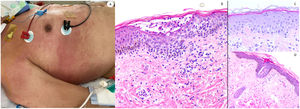

ResultadosLas lesiones de los casos se clasificaron de acuerdo con su característica clínica como vesiculares (4), erupciones maculopapulares (41) (figs. 2 y 3), lesiones urticariformes (9) (fig. 4) livedo y necrosis (10) (fig. 5) y tipo perniosis (5) (fig. 6).

Reacción maculopapular en un paciente en la Unidad de Cuidados Intensivos, que refleja pápulas eritematosas y púrpuras confluentes afectando principalmente costados y espalda, con vesículas escasas. A nivel histopatológico muestra una colección intraepidérmica de neutrófilos y células de Langerhans. Aparece una interfase vacuolar ligera, así como un infiltrado linfocítico perivascular ligero. El panel derecho muestra epiteliotropismo neutrofílico (imagen superior) y siringometaplasia ecrina en casos clínicamente similares, donde pueden observarse pocos neutrófilos en la epidermis superior, sin conformar pústula.